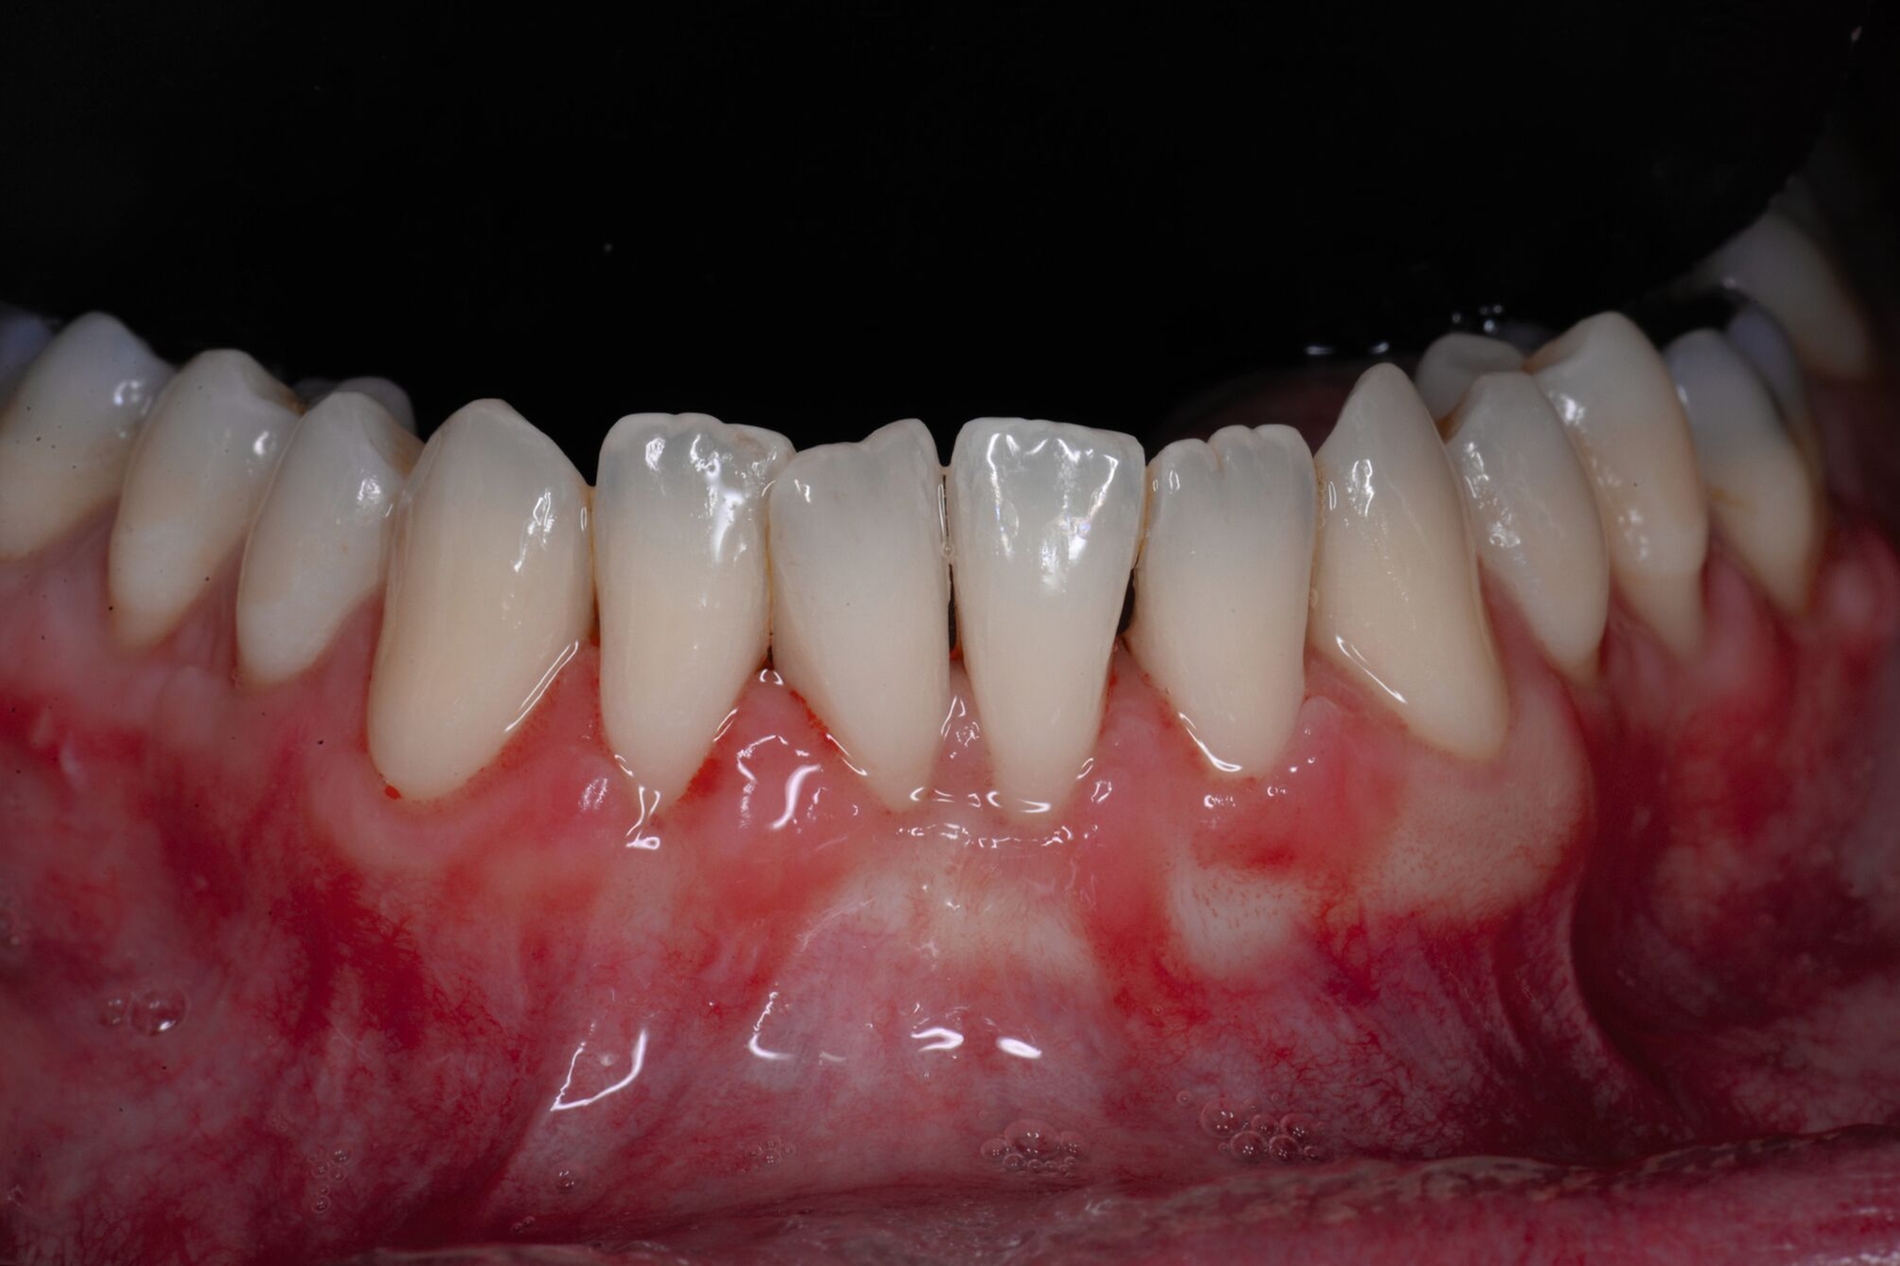

Der Lateral Geschlossene Koronal Verschobene Lappen ermöglicht eine annähernd narbenfreie Deckung singulärer parodontaler Rezessionen durch Verzicht auf vertikale Entlastungsinzisionen (Abbildung 3g). Das Lösen der Papillen im Rahmen der Verschiebung ermöglicht eine deutliche Anhebung des Lappens und somit durch großzügige Überdeckung das Erreichen vollständiger Wurzeldeckungen. Durch den lateralen Verschluss im Rahmen der tiefen, über die mukogingivale Grenze hinausgehenden Rezession kann keratinisierte Gingiva im Bereich dieser hergestellt und eine übermäßige Mobilisation und damit Einschränkung des Vestibulums verhindert werden.

Weiterer Bekanntheit erfreut sich der Lateral Geschlossene Tunnel (LCAT) nach Sculean & Allen [Sculean und Allen, 2018; Sculean et al., 2021]. Diese Methode zeigt durch das fast völlige Ausbleiben postoperativer Vernarbungen einen deutlichen Vorteil gegenüber den oben genannten Verfahren. Allerdings weisen Patienten nach Tunneltechniken verglichen mit Verschiebelappen tendenziell eine größere postoperative Morbidität auf. Nachteil der Tunneltechniken ist zudem die eingeschränkte koronale Verschiebbarkeit, die mit einer geringeren Quote mittlerer und vollständiger Wurzeldeckungen einhergeht [Pini Prato et al., 2005; Salhi et al., 2014; Santamaria et al., 2017; Neves et al., 2020]. An dieser Stelle setzt der Lateral Geschlossene Koronal Verschobene Lappen (LCAF) nach Tunkel an [Tunkel et al., 2024]. Anders als beim LCAT werden hier auch die Papillen vom interdentalen Col gelöst, so dass ein wirklicher Verschiebelappen gebildet wird. Dies ermöglicht eine Überdeckung der Schmelz-Zement-Grenze von mehr als 2 mm, so dass die vollständige Wurzeldeckung vorhersagbarer erreicht werden kann. Die vorübergehende sichtbare Lappen-Grenzlinie im Bereich der Papillen ist nach drei bis zwölf Monaten in der Regel ohne weitere Maßnahmen annähernd vollständig verschwunden, so dass auch hier ein Ergebnis visueller Narbenfreiheit erwartet werden kann. Ansonsten ist das Funktionsprinzip des LCAF vergleichbar mit dem LCAT. Im Gegensatz zum LCAT existieren vom LCAF allerdings noch keine klinischen Fallstudien, Fall-Kontroll-Studien oder gar randomisierte, kontrollierte klinische Studien, so dass die wissenschaftliche Evaluation dieser Methode noch abgewartet werden muss.